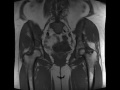

Mazabraud Syndrome

56-year-old female with chronic right hip pain. There are two circumscribed T1-hypointense, STIR-hyperintense lesions in the right hemipelvis. The first lesion is centered within the right iliac bone superior to the acetabulum with well circumscribed margins, no diffusion restriction, and minimal peripheral nodular enhancement. The second well circumscribed lesion is centered within the right gluteus medius muscle belly with circumscribed margins, no diffusion restriction, and minimal heterogeneous enhancement. Imaging findings within the right iliac bone are compatible with cystic fibrous dysplasia while those in the right gluteus medius muscle are compatible with a soft tissue myxoma. This is a patient with a known history of Mazabraud syndrome which consists of fibrous dysplasia with multiple soft tissue myxomas. Mazabraud syndrome is more frequent in women and usually presents in middle age. There is increased risk of osseous malignant transformation.